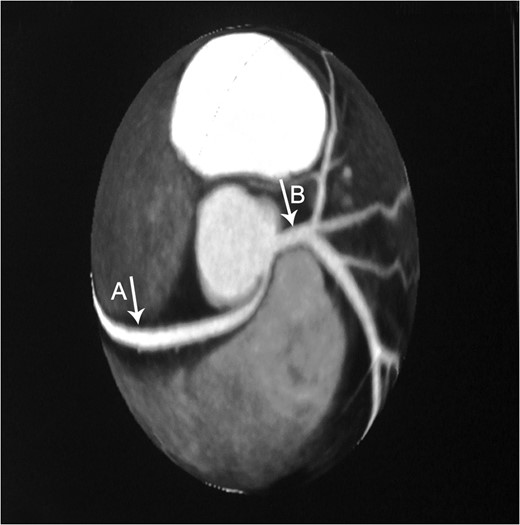

Axial CTA demonstrates an anomalous origin of RCA (Arrow A) which arises as a branch from LMCA (Arrow B).

This previously asymptomatic 37-year-old patient presented with continuous complaints of dyspnea on exertion associated with chest pain. Making her candidate for CTA which demonstrated the very rare anomalous origin of the RCA as a proximal branch from the LMCA that then continues between the pulmonary artery and ascending aorta where it is slightly compressed during systole. This finding provides us with the explanation of the presenting symptoms of such a case, which is supported by Grollman et al. ateriographic study [5].